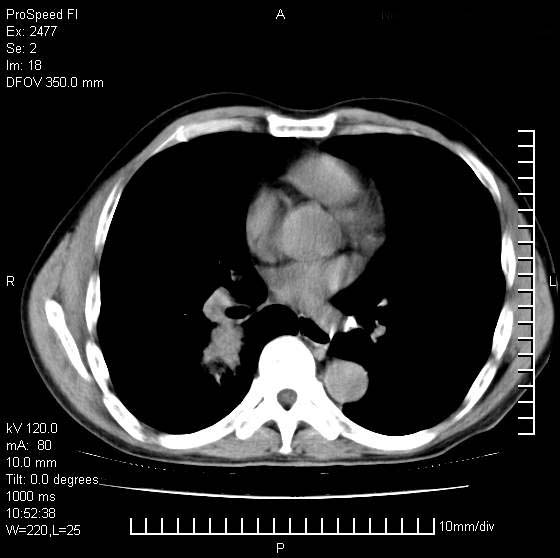

以下是引用天南地北在2007-10-9 14:29:00的发言:[br]1:右上肺结核[br]2:右肺下叶肿块:不支持肺癌,首先考虑炎性病变-肺脓疡可能性大[br]理由:1:临床病史支持,肺脓肿症状不明显应该是不规则服药造成。[br] 2:肿块边缘模糊,周围可见炎性渗出,长毛刺,内见支气管征,不过有点不规则。[br] 我感觉下肺癌这个诊断有点偏左,建议积极抗炎治疗后复查

以下是引用卜一在2007-10-9 15:55:00的发言:[br][br] [br] 1:右上肺结核[br]2:右肺下叶肿块:不支持肺癌,首先考虑炎性病变-肺脓疡可能性大[br]理由:1:临床病史支持,肺脓肿症状不明显应该是不规则服药造成。[br] 2:肿块边缘模糊,周围可见炎性渗出,长毛刺,内见空气支气管征,不过有点不规则。[br] 我感觉下肺癌这个诊断有点偏左,建议积极抗炎治疗后复查![br]支持! [br] [br] [br]

以下是引用wxy7406在2007-10-9 21:02:00的发言:[br]结合临床病史首先考虑感染性病变,但周围型肺癌不能除外,1.患者年龄偏大2.临床有咯血3.(也觉得是最重要的一点)病灶内有偏心性空洞。

以下是引用王仕学在2007-10-9 13:48:00的发言:[br]右下肺周围性肺癌可能性大,最好活检吧

以下是引用hhcckk在2007-10-9 15:18:00的发言:[br]右上肺病灶考虑结核,病灶多种形态并存(纤维化、增殖性病灶并存)[br]右下肺病灶比较难说,个人意见更趋向于“天南地北”的诊断----肺脓肿[br]1、病人有明显的寒战,高热,肿瘤病人很少出现[br]2、病灶周围的肺纹理走向柔和,没有肿瘤病灶常见的集束征[br]3、病灶边缘的毛刺较长,恶性肿瘤多为短毛刺[br]痰中血丝和病人的年龄是两个不利于良性肿块的因素,建议早点活检

以下是引用ydx_74在2007-10-9 15:53:00的发言:[br]右上肺结核,右下中心性肺癌可能大,肺门淋巴结肿大。